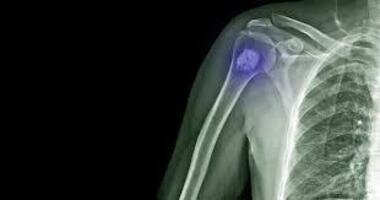

En el último episodio de Artro Esport Podcast, explicamos qué es la metástasis ósea: cuál es su origen, cómo se trata y cuál suele ser el perfil del paciente. Descubre todo en nuestro podcast.